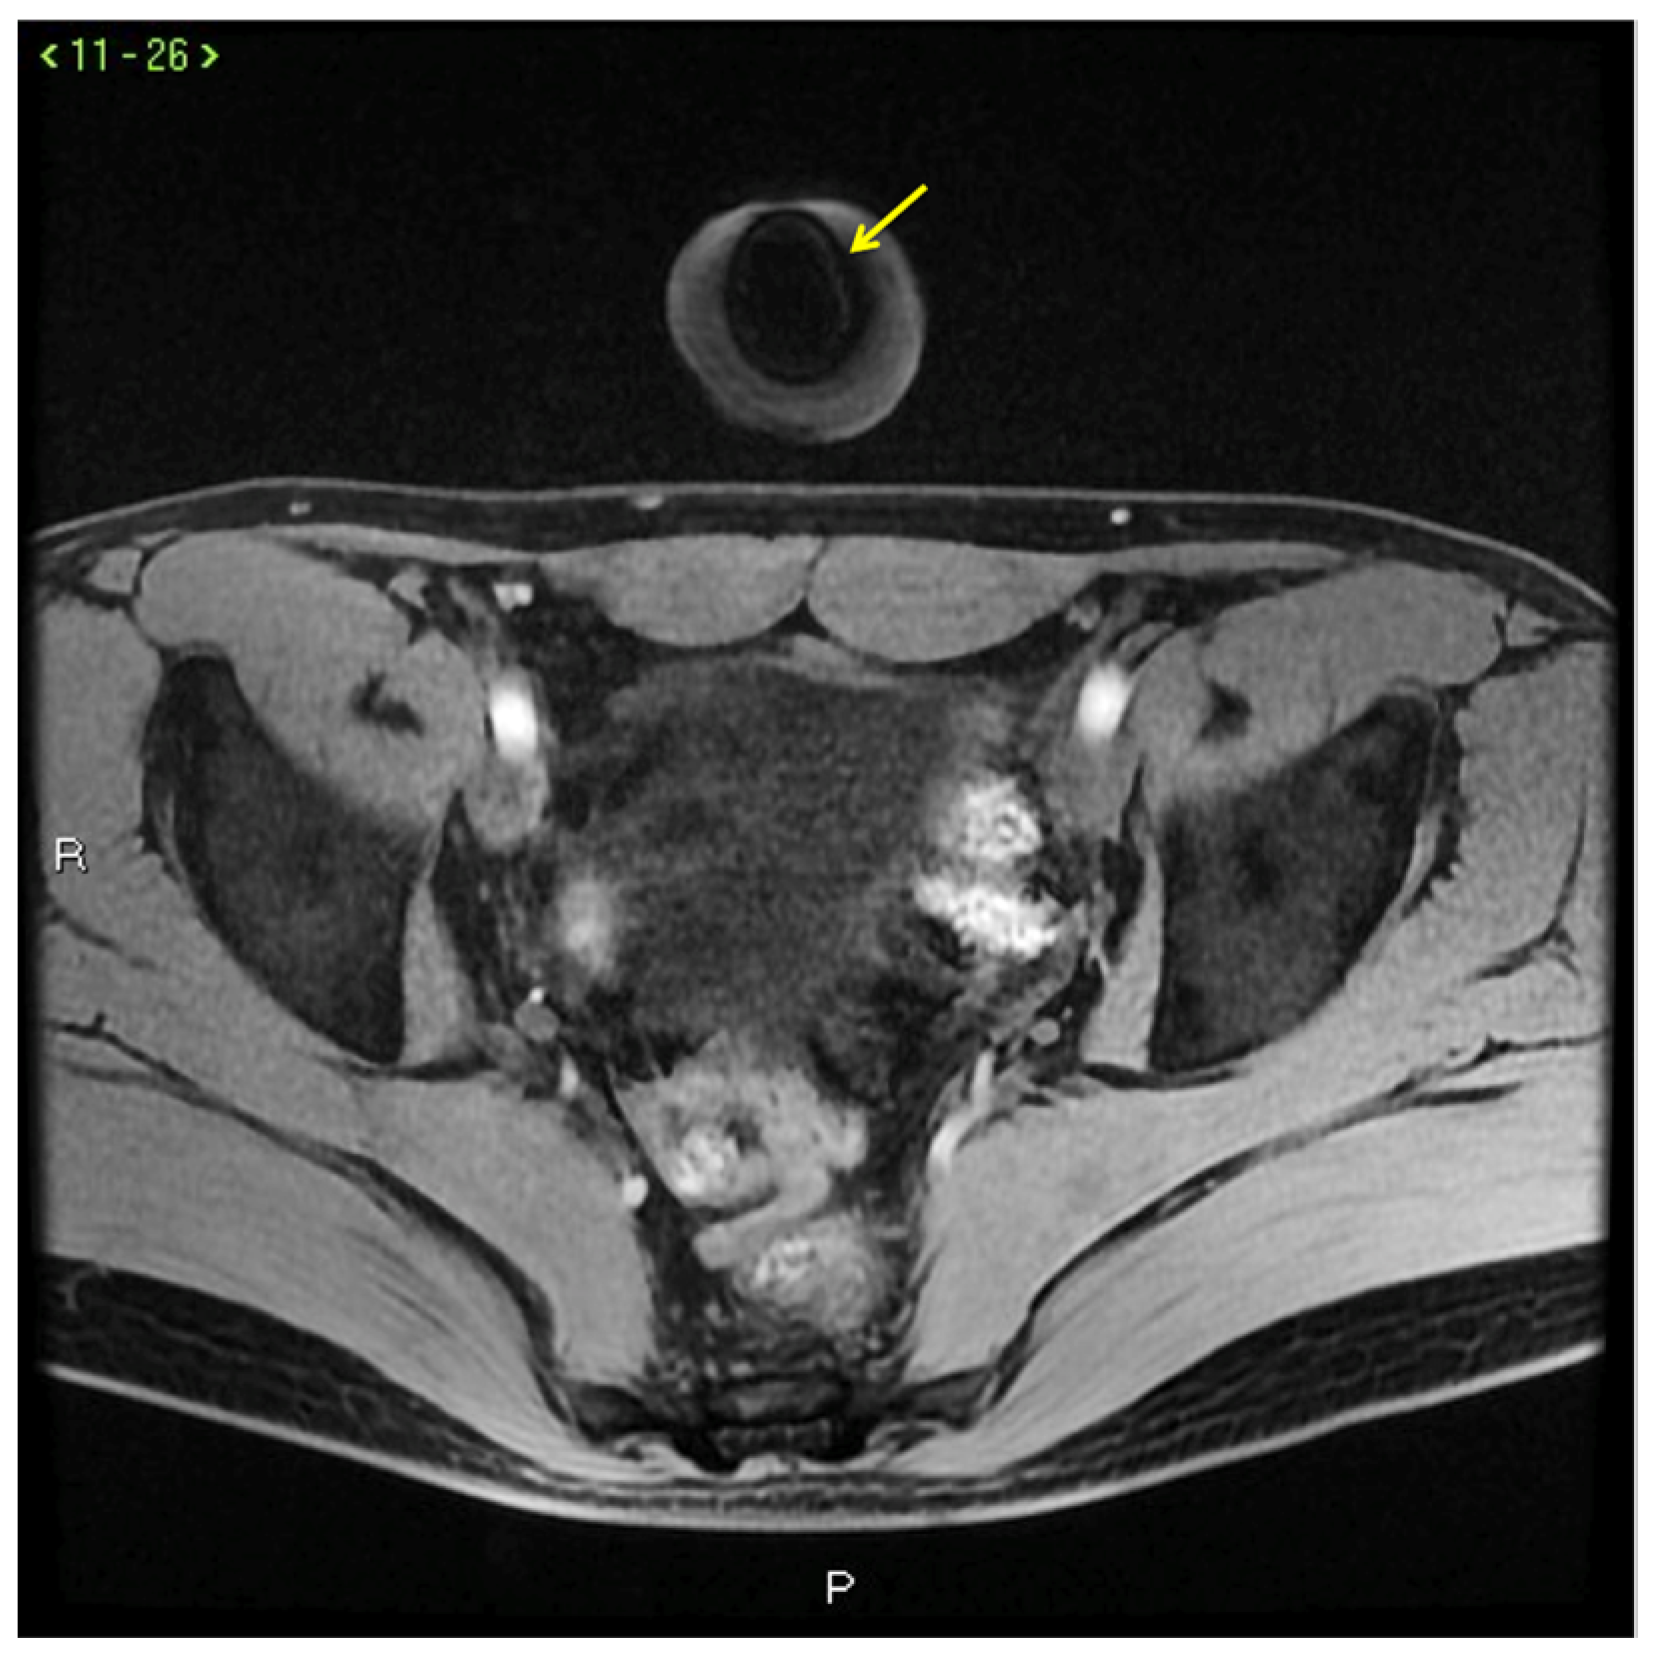

Figure 9.

Cav-MRI. The GRE T1W 3D FS axial images displayed with MIP reconstruction after 1 min (a) and 5 min (b) from the intracavernosal injection of the contrast agent show an ineffective penis erection sustained by venous leakage mediated by the deep dorsal vein of the penis ((a), arrowhead) that feeds the obturator veins ((b), arrows). The 3D Volume-Rendering (c) reconstructed 1 min after the administration of the contrast agent documents the rapid penis detumescence with a dominant deep dorsal venous collector (arrow).